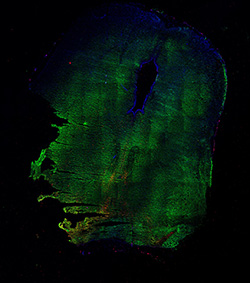

Merged

6PCW human midbrain